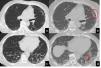

The UIP pattern represents the final step of the ageing process following maladaptive repair that induces alterations in both the airway cellular composition and function. Therefore, if the healthy distal airway epithelium is composed primarily of mucus-producing and multiciliated cell populations, patients with IPF show misexpression of mucus and aberrant ciliation. Consequently, these patients show increased wall thickness and architectural distortion of the distal airways on multidetector CT scans, which can be more precisely visualised on micro-CT images. Micro-CT scans of the explanted lungs of patients with IPF show dramatic loss of the terminal bronchioles and a significant decrease in the alveolar surface.136 Repeated aberrant attempts at regeneration of the terminal airways through the activation of developmental pathways result in honeycomb cysts.113 The stereological analysis of HC has confirmed its spatial relationship with small conducting airways. The corresponding multidetector CT findings include an increase in the number and degree of distorted airways in the 14th to 17th generation.137 Another macroscopic consequence of this metaplastic lining process the progressive bronchiolisation of the periphery of the lungs, with traction bronchiectasis beginning to appear beneath the pleura and, over the course of the remodelling, tending to assume the aspect of HC over a continuum of aberrant lung remodelling.138 Moreover due to the large and scarcely flexible space incapable of gas exchange, another immediate consequence is the loss of elastic recoil and the collapse of HC during the maximal expiration, which has been documented by CT expiratory scans (Fig. 5).

Inspiratory (a,c) and espiratory CT scan (b,d) shows UIP pattern characterized by the presence of honeycombing in the anterior segment of the left upper lobe, traction bronchiectasis and focal fibrotic ground glass in the left lower lobe. A mild peripheral reticulation is also present in the right lung parenchyma. The expiratory scan (b,c) shows a homogenous reduction in lung volumes associated with a diffuse increase of the lung density, in absence of air trapping. Interestingly, the area of honeycombing doesn't collapes (red ellipse). Moreover, the focal ground glass surrounding traction bronchiectasis, shows a lack of traction bronchiectasis collapse (red arrow).